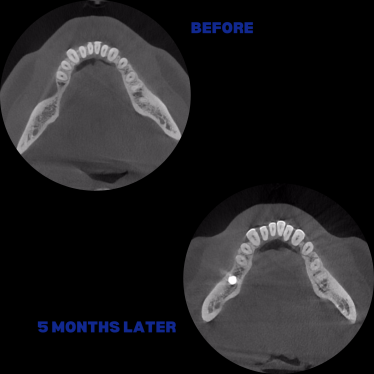

İmplant etrafındaki kemik açıklığını kemik grefti ile tedavi ettiğimiz vakamız